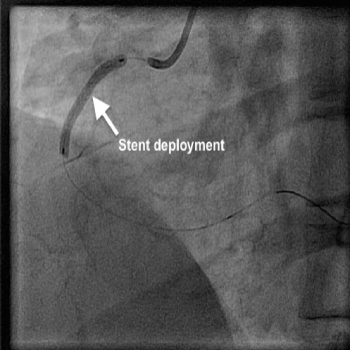

Her coronary angiogram, which was performed via right radial approach showed a totally blocked artery (right coronary artery) with plenty of thrombus, as expected. It was decided to perform angioplasty and therefore a wire was passed to cross the occlusion, which was successful. Then a thrombus aspiration catheter was inserted into the RCA, and a long serpentine clot was removed from the RCA. Further to this blood flow was established in the RCA, which showed a long segment of underlying narrowing of 70%. An OCT (optical coherence tomography) catheter was passed to assess the narrowing and size of the artery to decide about the stent. Then a drug coated stent was deployed in the narrowing to remove the block which was successful. This established a normal and brisk flow in the artery.